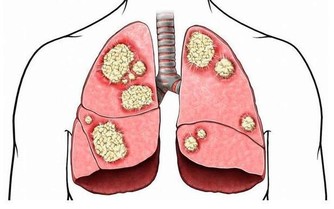

腸癌患者體內的腫瘤會阻塞腸道,妨礙糞便通過,進而導致便秘。

除了排便習慣的改變,結腸癌患者還有可能出現便血、腹痛、疲倦乏力、體重驟減等病症。